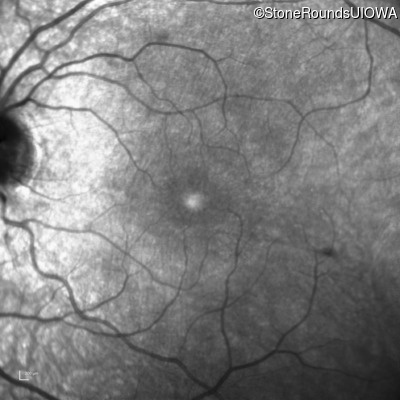

Infrared Fundus Photograph - Right - 20/40 -2

Exemplar